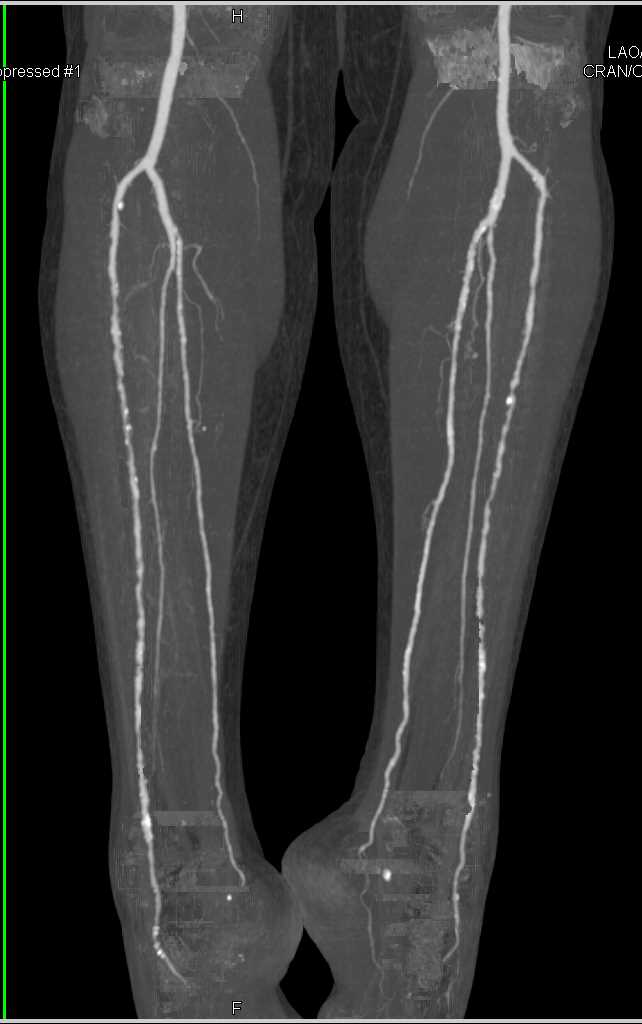

CTA Runoff with DE and Perioheral Vascular Disease